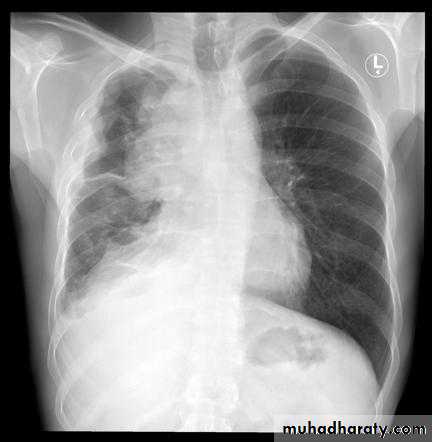

CXR & CT: it appears as a small well circumscribed mass or a bulky lobulated mass confluent with adjacent mediastinal structures

Imaging including CXR, CT, MRI.

2-Local mass effect: cough, dyspnea, hemoptysis, SVC obstruction